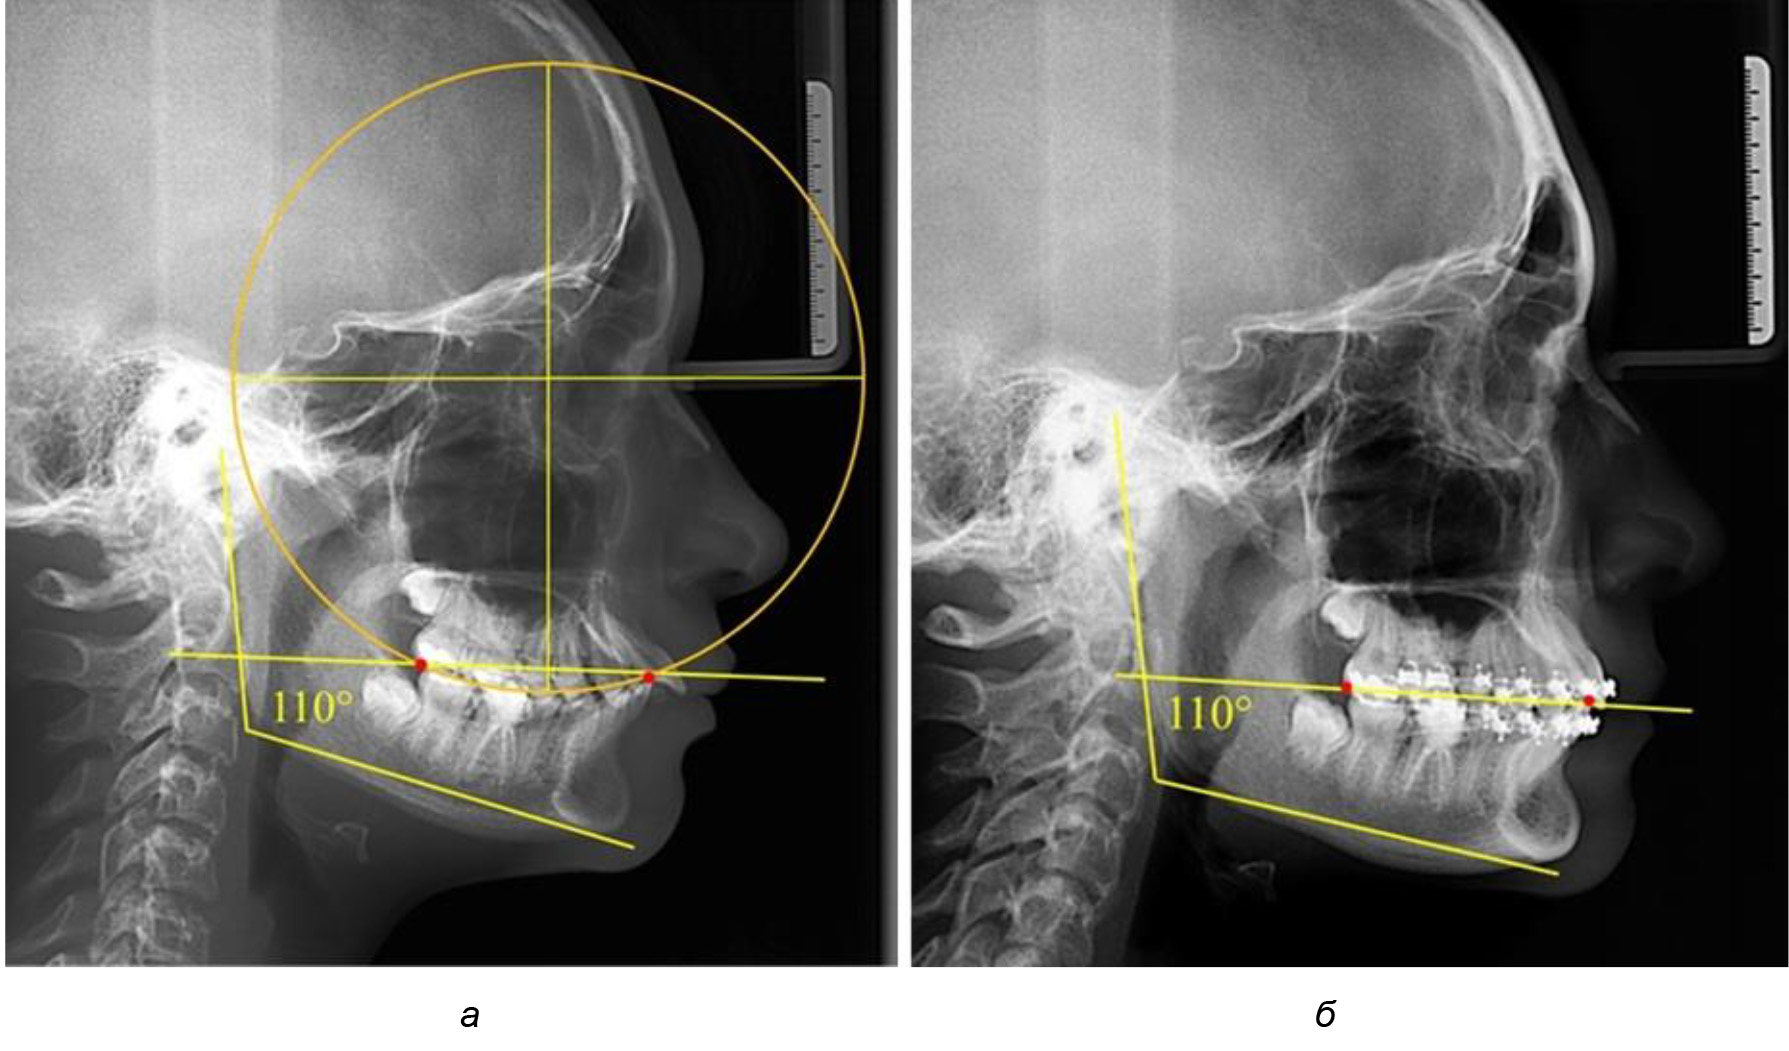

В 3-ю подгруппу вошли ТРГ и ОПТГ 14 человек 1-й группы, что составило (22,58 ± 5,31) % от общего количества людей 1-й группы. Величина угла нижней челюсти в среднем составила (114,85 ± 2,87)° и характеризовала горизонтальный тип нижней челюсти.

Глубина кривой Spee в среднем по 2-й подгруппе составил (2,94 ± 0,47) мм, что было меньше, чем в других подгруппах. Деление величины радиуса круга к длине окклюзионной линии составило 1,616 ± 0,02 (рис. 4).

Рис. 3. Особенности кривой Spee на ТРГ (а) и ОПТГ (б) при нейтральном типе роста нижней челюсти

Рис. 4. Особенности кривой Spee на ТРГ (а) и ОПТГ (б) у людей с горизонтальным типом лица